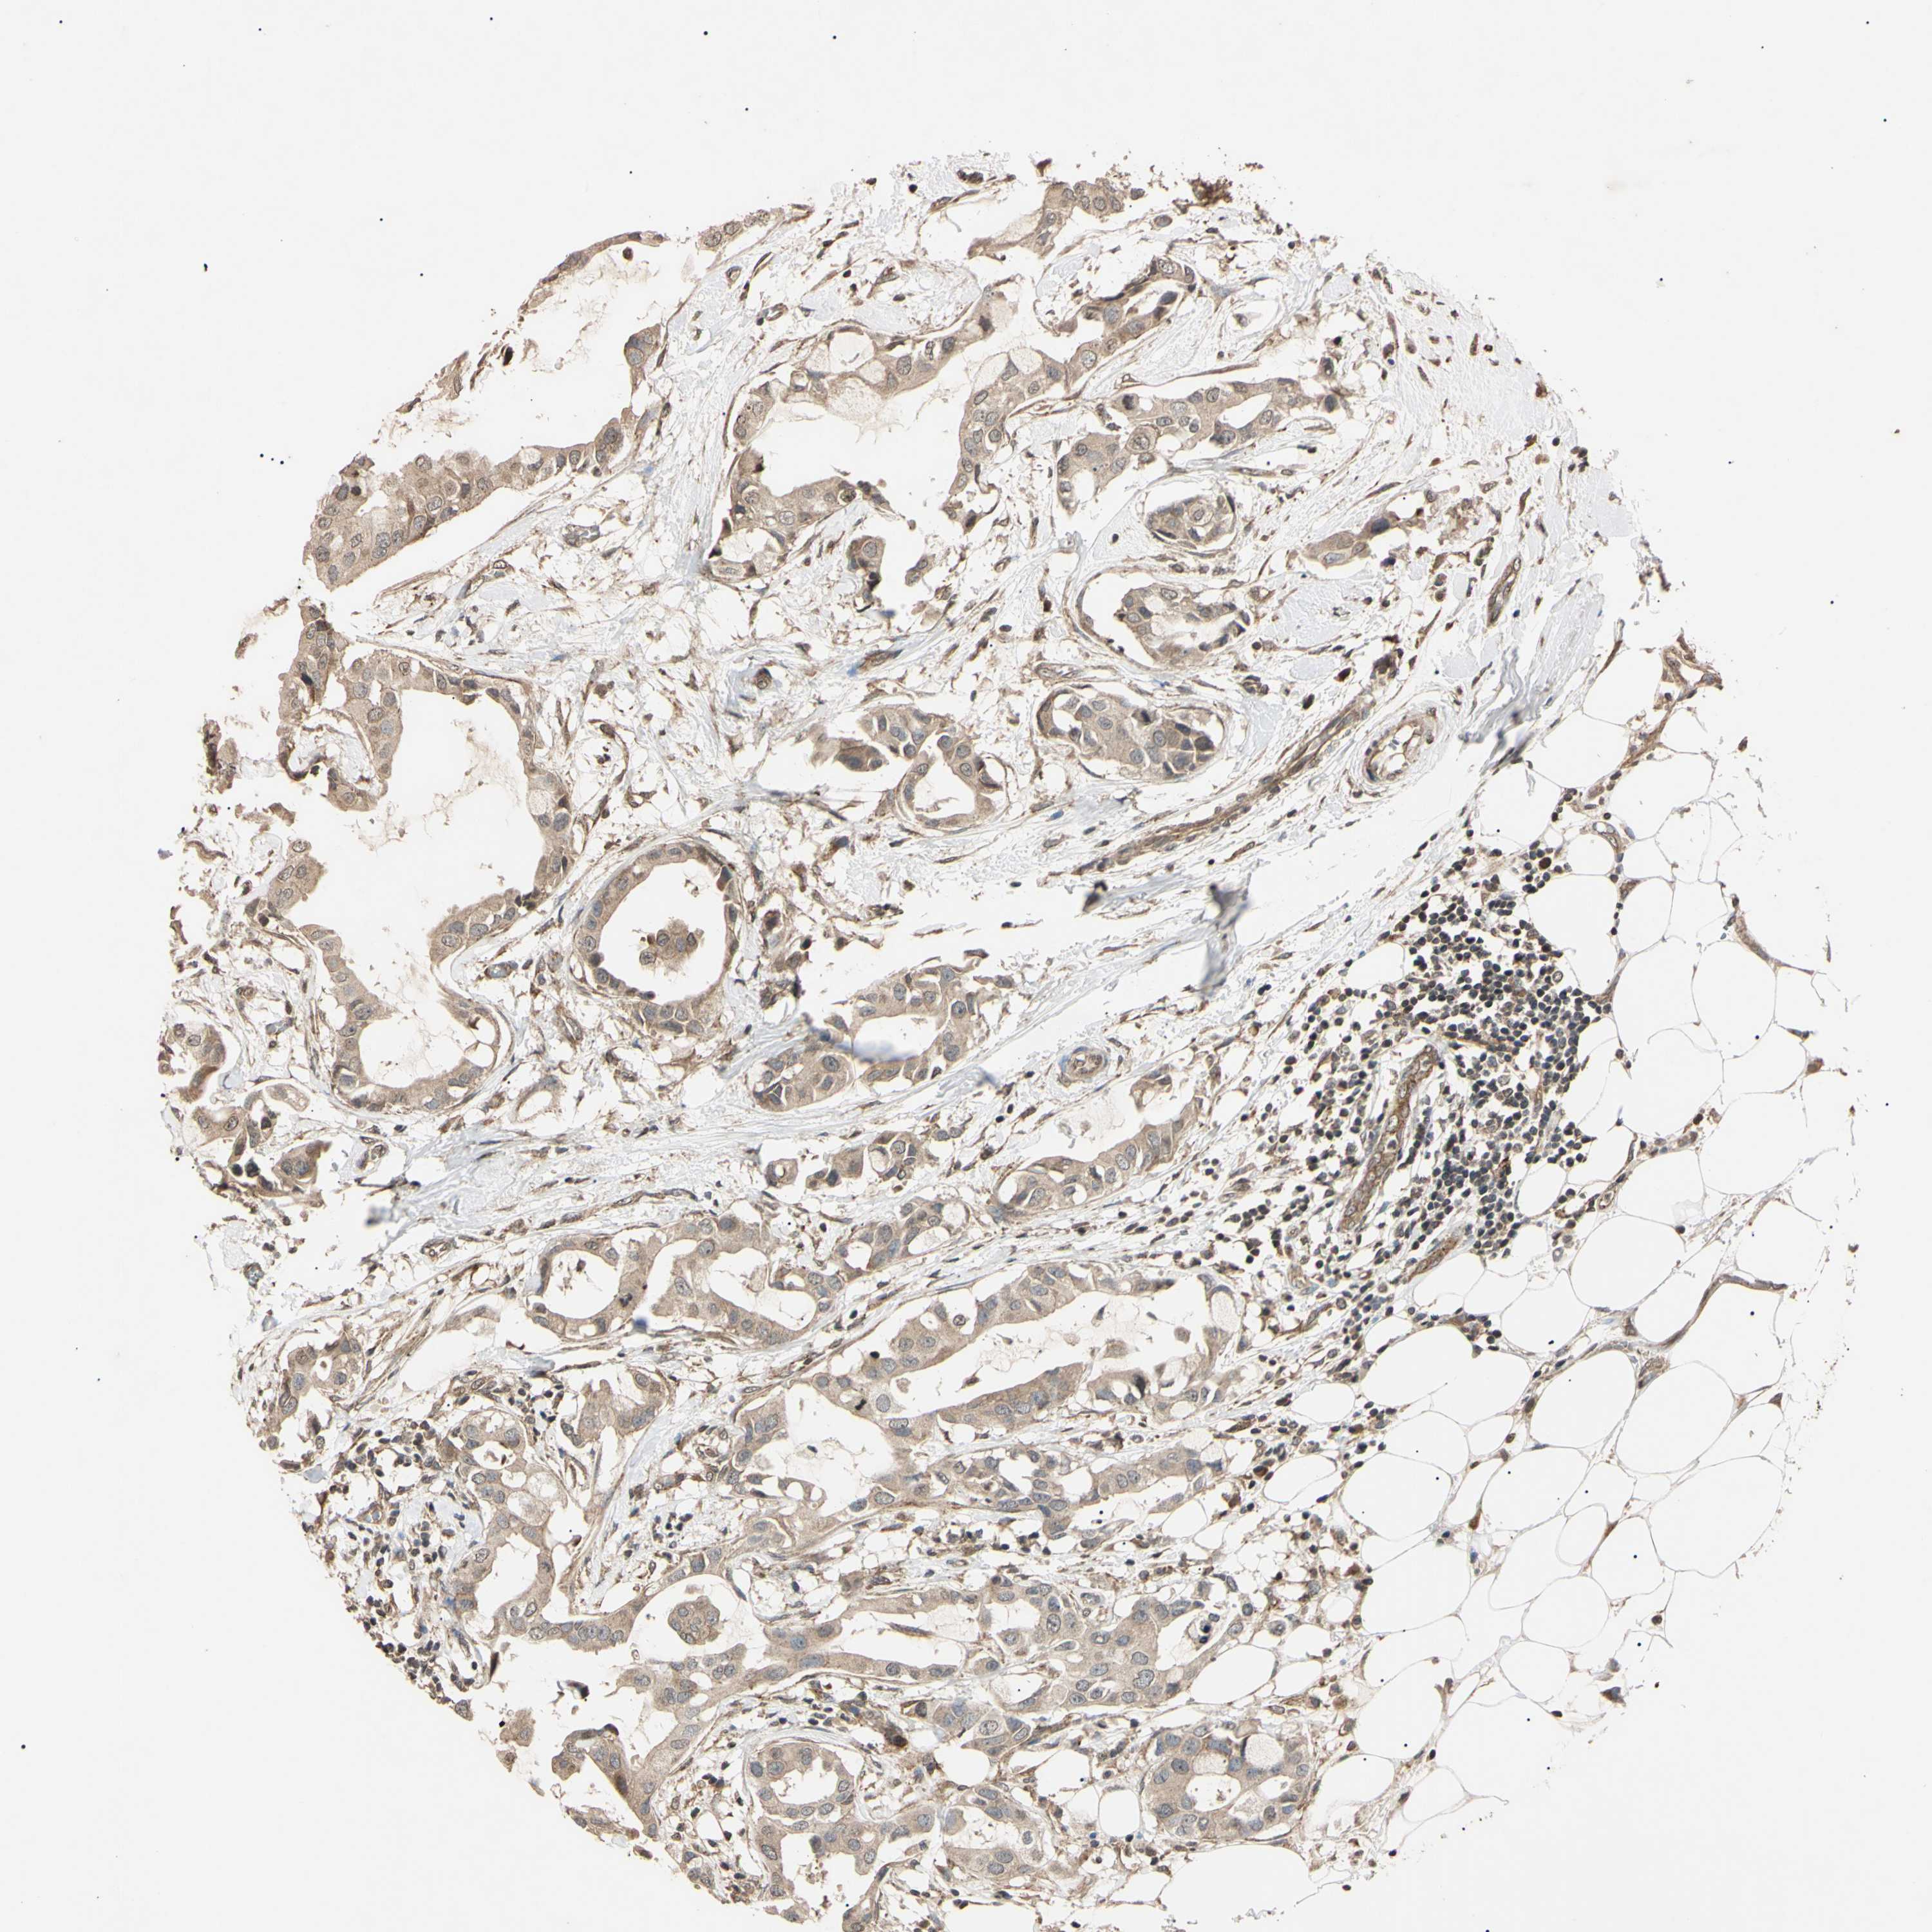

CANCER BREAST CANCER Show tissue menu

BRCA TCGA BRCA VALIDATION PROTEIN EXPRESSION